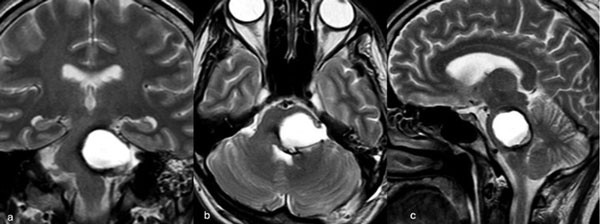

Figura 5. RM postquirúrgica de encéfalo. Se evidencia una exéresis completa con hiperintensidad en T2 en regresión. A, B y C) Imágenes ponderadas en T2 en cortes coronal, axial y sagital, respectivamente.

Caso 3: cavernoma pontino

Un hombre de 37 años, con antecedentes de hipertensión arterial, debutó con ataxia de la marcha, nistagmo y hemihipoestesia facial izquierda y braquiocrural derecha. La RM de encéfalo evidenció una malformación cavernomatosa centrada en la protuberancia y el pedúnculo cerebeloso medio izquierdo (Figura 6). Un mes después del sangrado, el paciente fue sometido a una exéresis de la lesión mediante un abordaje retrosigmoideo ampliado por izquierda a través del pedúnculo cerebeloso medio (Figura 7), logrando una exéresis completa (Figura 8). Después del procedimiento, el paciente evolucionó con persistencia de los síntomas de ingreso, pero sin agregar nuevos déficits.

Figura 6. RM preoperatoria de encéfalo. Se evidencia una lesión única intraaxial localizada en el puente y pedúnculo cerebeloso medio izquierdo, hiperintensa en T1 y con un anillo hipointenso en T2, característica de una malformación cavernomatosa con sangrado reciente. A) Imagen ponderada en T1 en corte sagital. B y C) Imágenes ponderadas en T2 en cortes axial y coronal, respectivamente.

Figura 7. Imágenes intraoperatorias bajo microscopía. Abordaje retrosigmoideo ampliado a izquierda, con ruta de ingreso transpedúnculo cerebeloso medio. A) Apertura de fisura horizontal que divide los lóbulos semilunar superior y semilunar inferior del cerebelo, exponiendo el pedúnculo cerebeloso medio. B) Corticotomía en pedúnculo cerebeloso medio, evidenciando la cápsula del cavernoma. C) Resección en bloque de la malformación cavernomatosa. D) Revisión del lecho, sin remanente.

Figura 8. RM postquirúrgica de encéfalo. Se evidencia una exéresis completa, sin daño del parénquima adyacente. A, B y C) Imágenes ponderadas en T2 en cortes coronal, axial y sagital, respectivamente.